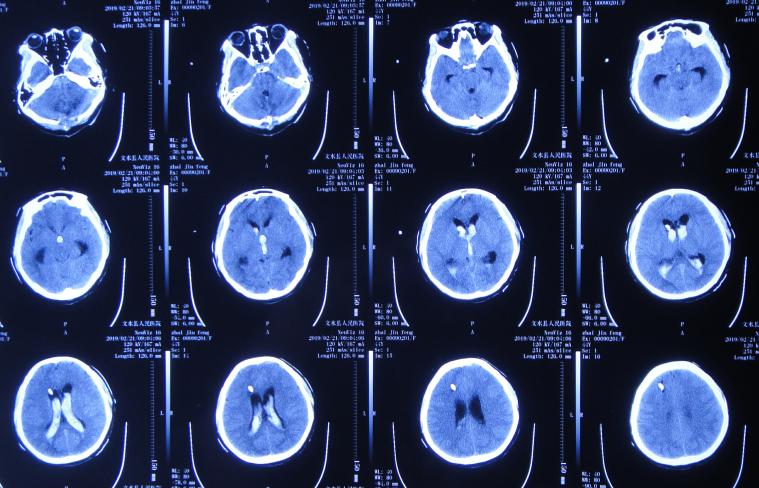

但脑出血脑室外引流术3天即2019年2月21日,出现尿崩症状,查头颅CT示脑室仍有出血( 图-4 );给予口服弥凝2天后症状好转,查血电解质示低钠、低钾,但给予积极纠正但效果仍不理想。

图-4: 2019年2月21日头颅CT